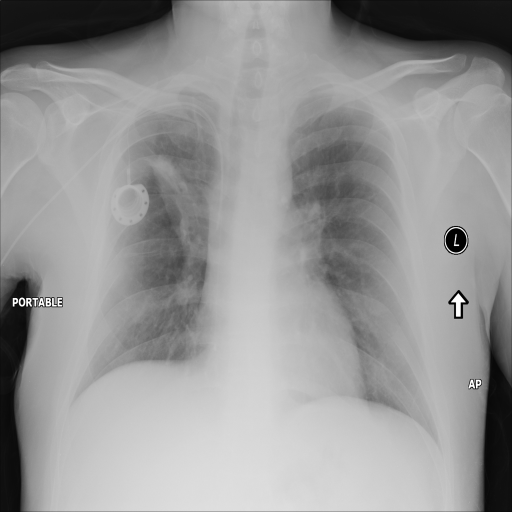

In Fig. 1, we show four ϵitalic-ϵ\epsilon-LDP-processed CXR images of clinical cases obtained with the image domain LDP, which directly imposes the Laplace mechanism on the input image, with different privacy budgets together with the original images. Fig. 2 shows four ϵitalic-ϵ\epsilon-LDP-processed CXR images of clinical cases obtained with DP-GLOW and different privacy budgets together with the original images. In case 1 for DP-GLOW, there is decreased permeability in the bilateral hilar regions. Although this hilar opacity tends to be preserved with a larger privacy budget, the entire image is degraded when the privacy budget becomes 101HWsuperscript101𝐻𝑊10^{1}\cdot H\cdot W. A similar tendency is observed in the images of all the four cases for DP-GLOW; for example, in case 4 with ϵ=101HWitalic-ϵsuperscript101𝐻𝑊\epsilon=10^{1}\cdot H\cdot W, the lung opacity suggesting pneumonia in the right lower lung field is well preserved, while the entire image is degraded.

Refer to caption

(a) Original

case 1

(b) ϵ=103HWitalic-ϵsuperscript103𝐻𝑊\epsilon=10^{3}\cdot H\cdot W

(c) ϵ=102HWitalic-ϵsuperscript102𝐻𝑊\epsilon=10^{2}\cdot H\cdot W

(d) ϵ=101HWitalic-ϵsuperscript101𝐻𝑊\epsilon=10^{1}\cdot H\cdot W

Figure 2: ϵitalic-ϵ\epsilon-LDP-processed CXR images obtained with DP-GLOW.